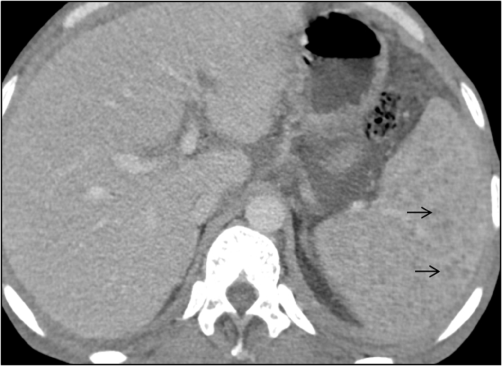

The scan was done on 128 slice Siemens CT scan machine, which revealed moderate hepatomegaly with liver measuring 17.5cm in craniocaudal dimension (Figure 1A). There were multiple conglomerated and enlarged lymph nodes with internal low attenuating areas (signify necrosis) observed in pre-para aortic, aortocaval and mesenteric regions (Figure 1B), largest measuring (20x11)mm in the right iliac fossa. The spleen was also enlarged with numerous tiny hypodense peripherally enhancing lesions diffusely scattered in its parenchyma (Figure 2). A minimal amount of free fluid was noted in the peritoneal cavity. The CT scan also demonstrated multiple centrilobular nodular densities arranged in linear branching patterns forming tree-in-bud appearance and patchy areas of consolidations in the limited scan of the bilateral lung fields (Figure 3A). Mild right-sided pleural effusions and left-sided empyema were also noted (Figure 3B).

Figure 2 Contrast enhanced computed tomography scan, venous phase in axial plane shows numerous tiny hypodense peripherally enhancing lesions diffusely scattered in splenic parenchyma consistent with tubercular micro abscesses (black arrows).